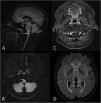

To describe the magnetic resonance imaging (MRI) findings for the most common inflammatory and immune-mediated diseases that involve the brainstem.

ConclusionInflammatory lesions involving the brainstem are associated with a wide range of autoimmune, infectious, and paraneoplastic syndromes, making the differential diagnosis complex. Being familiar with these entities, their clinical characteristics, and their manifestations on MRI, especially the number of lesions, their shape and extension, and their appearance in different sequences, is useful for orienting the radiological diagnosis.